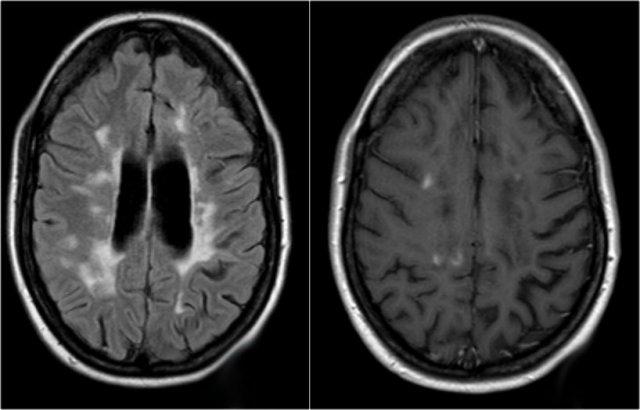

MRI não cho thấy các tổn thương quanh não thất và một tổn thương ở thể chai.

Các vị trí này rất đặc trưng cho MS.

Ở một bệnh nhân khác có các tổn thương không đặc hiệu trong tủy sống.

Chỉ dựa vào khảo sát cột sống đơn thuần, chúng ta có một chẩn đoán phân biệt rộng.

Tuy nhiên khi khảo sát thêm não, sẽ rõ ràng rằng chúng ta đang đối mặt với MS.

Tiếp tục xem các hình ảnh của não.

Trong trường hợp này, các hình ảnh trên não rất hữu ích.

Vị trí của các tổn thương rất điển hình: cầu não, quanh não thất và dưới vỏ não.